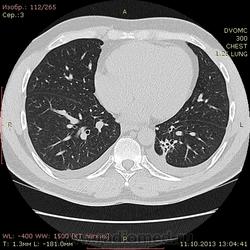

Пациент 35 лет. На УЗИ нашли житкость слева в плевральной полости, отправили на КТ - жидкость с обеих сторон. Из разговора с больным выяснилось, что около 1,5 месяцев назад была высокая тенпература, кашель - никуда не обращался и не лечился. На момент исследования ни на что не жалуется.

Похоже слева в S10? на поствоспалительные изменения? или на что похуже? И если на стороне поражения можно понять окуда жидкость, то справа - можно расценивать как реакция плевры на воспаление слева?

Локальный фиброз субсегмента S10 слева с бронхоэктазами. Двусторонний малый гидроторакс (толщина слоя жидкости до 1 см≈объём до 50 мл). Интересная субкапсульная ерундовина в S6 печени, наверное киста.